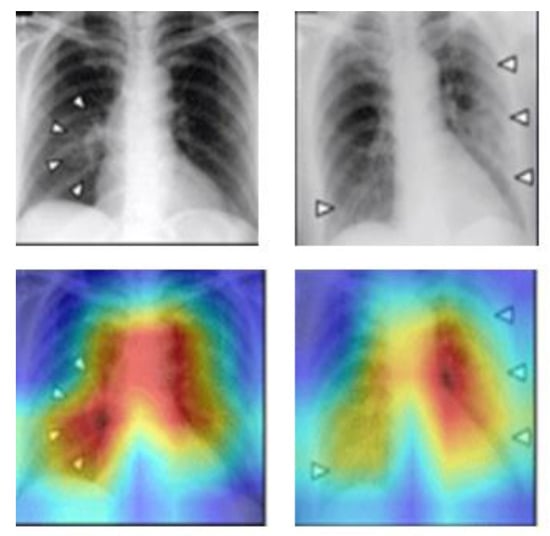

CAM is a CNN visualization technique introduced by B. Zhou et al. at the CVPR 2016 conference []. It was originally proposed to solve the problem of weakly supervised learning, where CNNs are capable of detecting and localizing objects even if they lack labeled location information during training. This ability is lost when the network uses the Fully Connected Layer, but replacing it with the Global Average Pooling (GAP) layer preserves the localization ability and reduces the overall network parameters. The CAM method can visualize the CNN network’s position of interest in classification and generate a heatmap for the overall object localization of the network. By combining CAM and GAP, the CNN can classify the image and locate specific areas related to the classification. For example, Figure 3 demonstrates the CAM schematic, where the CAM helps to identify the critical regions that need to be detected to diagnose COVID in the chest X-ray images.

Figure 3.

CAM schematic of chest-X ray, the critical regions are indicated by triangular arrows.